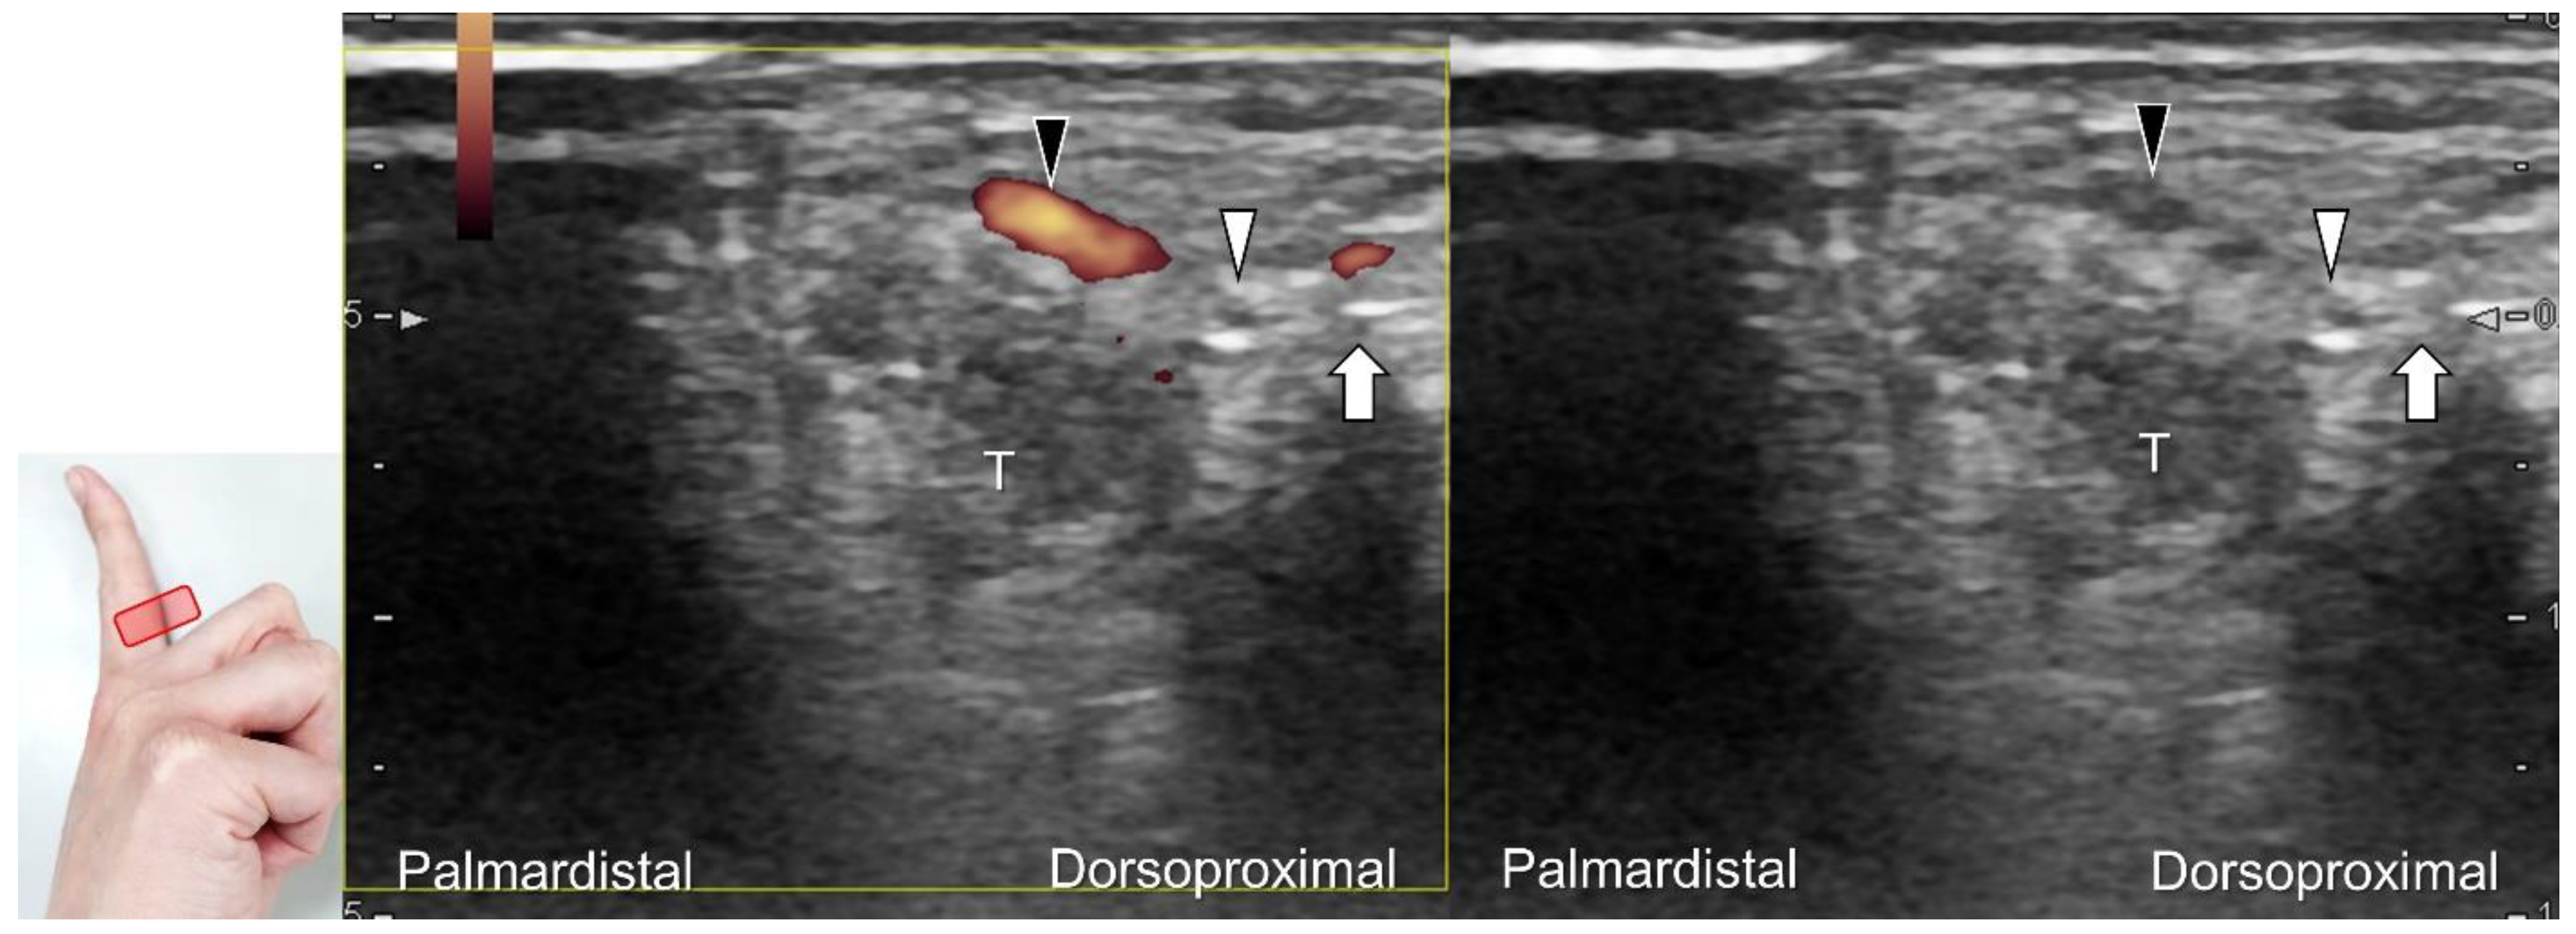

Figure 5. Comparative ultrasonography (long-axis view) between healthy (A) vs. affected (B) sides shows a schwannoma (black arrowhead) with increased intraneural vascularity.

Carpal tunnel syndrome is the most common entrapment neuropathy whereby the median nerve is entrapped by various causes, like hypertrophy of the flexor retinaculum (Figure 2C,D) and compression from the accessory muscles, swollen tendons, ganglions, and bony fractures within the tunnel. Ultrasonographic changes encompass swelling proximal to the entrapment site (Figure 3A), flattening over the entrapment site (Figure 3B), intraneural hypervascularity (Figure 3C), and focal loss of the trimline pattern (Figure 3D).

The nerve’s CSA (a cutoff value of 9–10.5 mm2) arises as the most useful parameter for the diagnosis [28], whereas its diameter, gliding resistance [29], stiffness (evaluated by sonoelastography), and intraneural vascularity (assessed by power Doppler imaging) may serve as adjuvant indicators. A bifid median nerve (Figure 4A), the presence of a persistent median artery (Figure 4B) with or without thrombosis, accessory flexor digitorum superficialis muscle (Figure 4C), laceration of the palmaris longus tendon (Figure 4D), and schwannoma (Figure 5) can be associated findings for carpal tunnel syndrome [9].